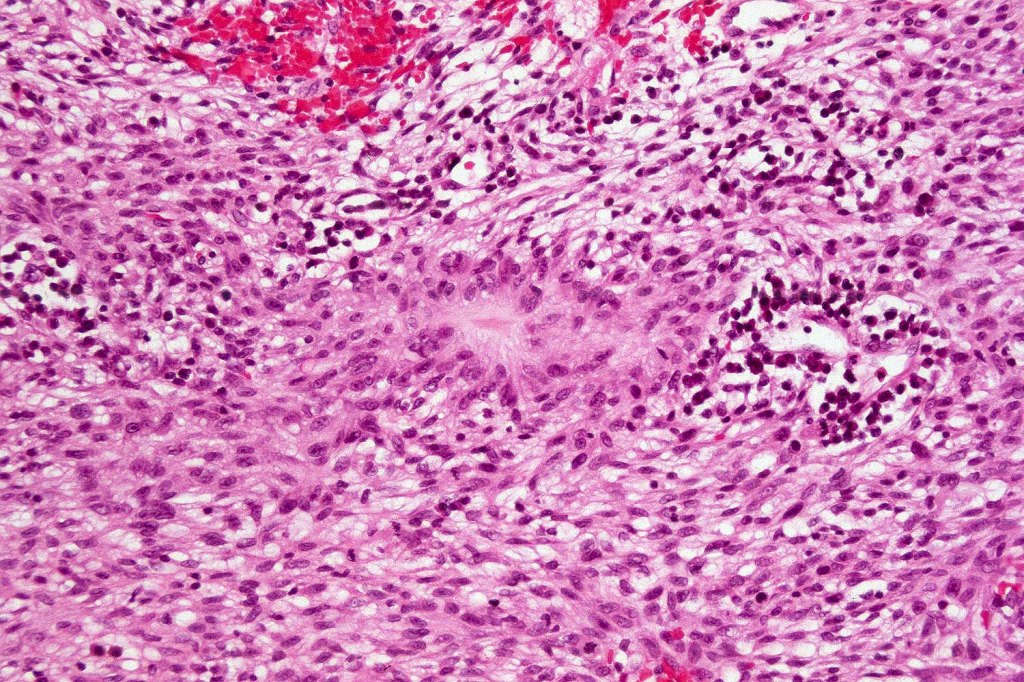

Carcinosarcoma

Cutaneous carcinosarcoma (metaplastic carcinoma, carcinoma with heterologous differentiation)

Histological features

•Osteoid

•Chondroid

•Smooth muscle

•MFH-like features with osteoclasts

•Neural differentiation